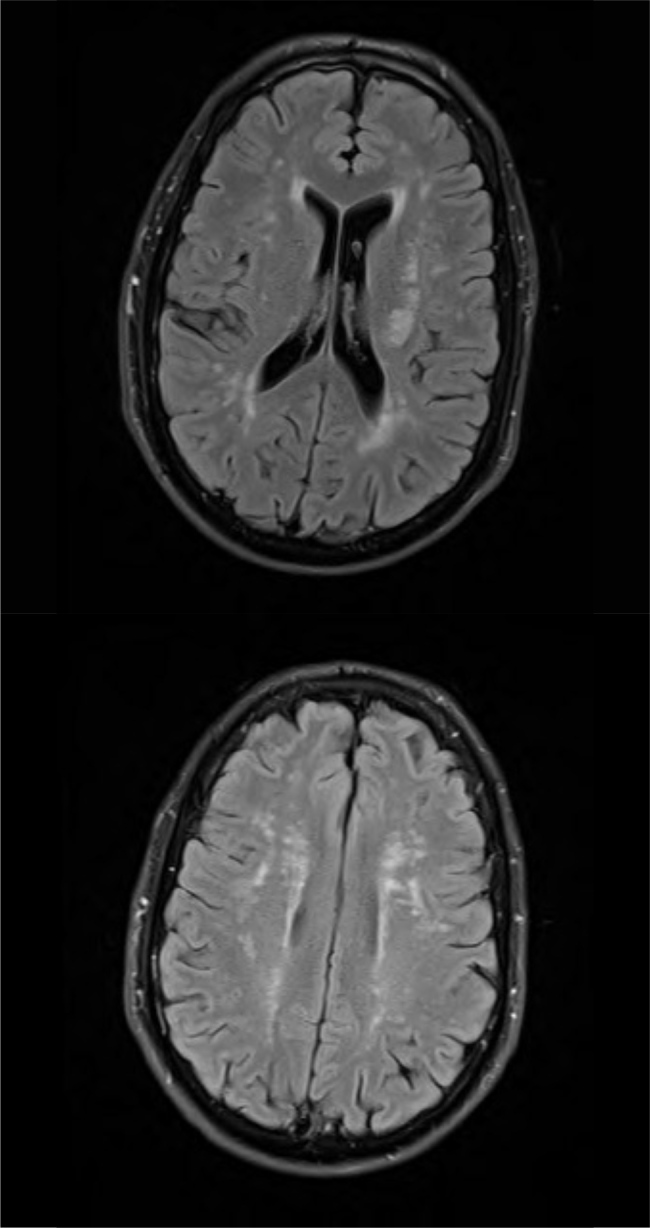

This report provides a detailed analysis of a singular case involving cerebral autosomal dominant arteriopathy with subcortical infarcts and leukoencephalopathy (CADASIL) in a male patient who suffered a stroke. Our investigation delves into the clinical manifestations, genetic foundations, diagnostic complexities, and prognosis associated with CADASIL. As a notable contributor to stroke occurrence in young patients, CADASIL's impact on morbidity and mortality is influenced by stroke-related complications and cognitive decline. Notably, our report highlights a novel genetic variant (C.3025T>C; p.Cys1009Arg) in the NOTCH3 gene linked to CADASIL, shedding light on its underlying pathogenesis. Furthermore, our patient exhibited unexpected white matter changes, challenging conventional age-related norms. These findings underscore the essential role of genetic testing and emphasize the potential diversity in CADASIL's clinical presentation. Further exploration is imperative to enhance our understanding of CADASIL and refine diagnostic strategies, thereby facilitating improved patient prognosis and management.

Learning points: Cerebral autosomal dominant arteriopathy with subcortical infarcts and leukoencephalopathy (CADASIL) is a significant cause of stroke in young patients, with stroke-related complications and cognitive impairment contributing to morbidity and mortality.Increasing awareness of CADASIL's clinical presentation and the availability of genetic testing has led to a rise in reported cases.CADASIL is caused by mutations in the NOTCH3 gene, primarily involving missense substitutions and leading to cysteine residue alterations.There have been many pathogenic variants reported around the world and some families might exhibit private pathogenic variants.